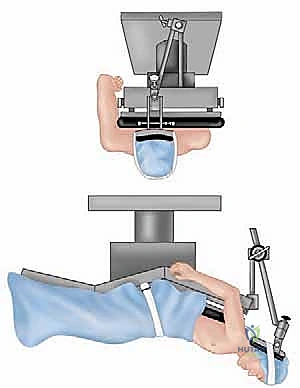

Patient positioning is a critical, often underappreciated aspect of a successful shoulder